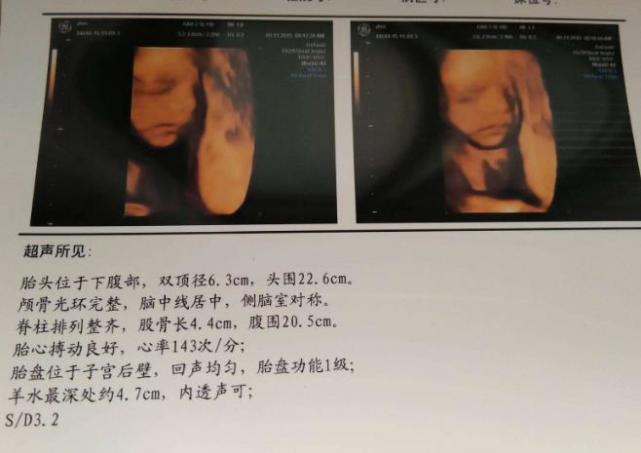

3、四维彩超单上的数字有什么意义?

做完四维彩超后,我们会拿到一个单子,这个单子上会显示很多数据,大部分人都表示看不懂。其实四维彩超单上的一些证据,你要学会看。比如说胎心正常范围是在120-160次/分,胎盘厚度在2.5-5.5cm之间,羊水深度在3-7cm时间,如果这些重要数据你都达标,那么就说明胎儿发育健康。